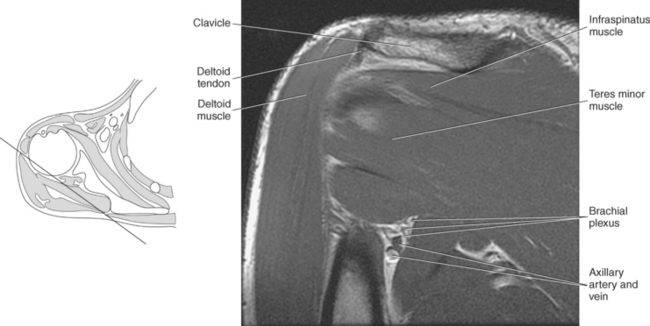

Muscles of the scapula are described in Table 9.2 and demonstrated in Figures 9.34 through 9.52. The large deltoid muscle originates on the clavicle, acromion, and scapular spine to blanket the shoulder joint as it extends to insert on the deltoid tuberosity of the humerus. This powerful muscle forms the rounded contour of the shoulder and functions primarily to abduct the arm (Figure 9.48). The teres major muscle is a flat rectangular muscle that adducts and medially rotates the arm. It extends from the inferior angle of the scapula to the medial aspect or lip of the intertubercular groove of the humerus (Figure 9.49, A). The four remaining muscles, supraspinatus, infraspinatus, teres minor, and subscapularis, closely surround the scapula and compose the rotator cuff (Figures 9.49 through 9.52). The rotator cuff provides dynamic stability to the shoulder joint and allows for adduction, abduction, and rotation of the humerus. The supraspinatus, infraspinatus, and teres minor muscles are located on the posterior aspect of the scapula. The tendons of these muscles insert on the greater tubercle of the humerus. The supraspinatus muscle lies in the supraspinous fossa of the scapula and helps to abduct the arm. The tendon of the supraspinatus muscle is the most frequently injured tendon of the rotator cuff because of possible impingement as it extends under the acromioclavicular joint and continues over the humeral head (Figure 9.49, B). The infraspinatus muscle is a triangular muscle that lies below the scapular spine in the infraspinous fossa. It acts to laterally rotate the arm (Figure 9.49, A). Lying along the inferior border of the infraspinatus muscle is the elongated teres minor muscle, which also acts to laterally rotate the arm (Figure 9.49, B). The subscapularis muscle is the only muscle of the rotator cuff located on the anterior surface of the scapula; its tendon inserts on the lesser tubercle of the humerus (Figures 9.50 through 9.52). The subscapularis muscle acts to medially rotate the humerus. See sequential images through the shoulder (Figures 9.34 through 9.47).